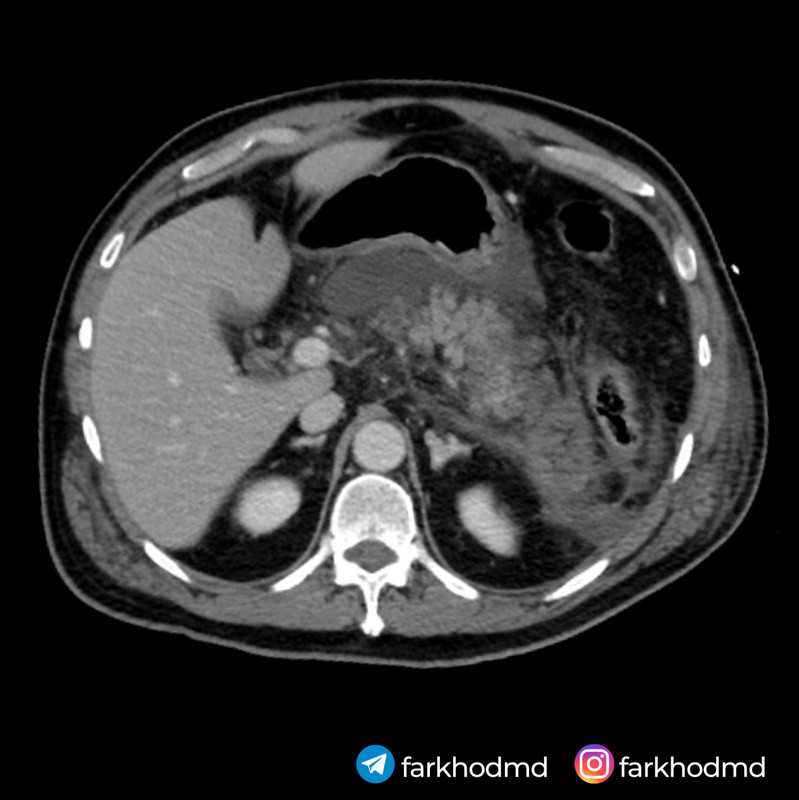

A 56-year-old man with a long history of heavy alcohol consumption presents to the emergency department with severe, persistent epigastric pain that started a few hours after a large evening meal accompanied by multiple beers. The pain radiates to his back, intensifies when supine, and is slightly alleviated by sitting forward. On examination, he appears acutely ill, with mild hypotension, tachycardia, and low-grade fever. His abdomen is markedly tender in the upper region, though without significant rebound tenderness. Laboratory tests reveal markedly elevated serum amylase and lipase. Serum glucose is also elevated. An abdominal CT scan is shown. Despite aggressive intravenous fluid resuscitation, pain management, and supportive measures, the patient rapidly deteriorates and dies within a short period of admission.

This patient’s presentation, marked by severe epigastric pain radiating to the back, elevated pancreatic enzymes, and hemorrhagic changes on imaging, reflects a severe acute inflammatory process within the pancreas. His longstanding heavy alcohol use sets the stage for pathophysiological alterations in the pancreatic acinar cells. Instead of enzymatic activation occurring normally in the intestinal lumen, the disruption of intracellular calcium signaling leads to premature enzyme activation inside the cell. As these enzymes become active prematurely, they begin digesting pancreatic tissue, causing inflammation, necrosis, and systemic complications. This cascade of intracellular events directly underlies the rapidly progressive and fatal outcome.

The key element driving this patient’s condition lies in the disruption of normal intracellular calcium signaling within pancreatic acinar cells. Under physiological circumstances, pancreatic enzymes like trypsinogen are secreted in an inactive form and only become active once they reach the duodenum. In the setting of heavy alcohol use, various factors, including altered intracellular calcium handling, trigger premature activation of these enzymes within the pancreatic acinar cell itself. Elevated intracellular calcium levels lead to the conversion of trypsinogen to trypsin prematurely, setting off a destructive cascade that causes autodigestion of the pancreatic tissue. This enzymatic injury results in necrosis of the acinar cells and subsequent release of proinflammatory cytokines.

These cytokines escalate the local inflammatory response and propagate tissue injury, contributing to systemic inflammatory response syndrome (SIRS) - which the patient most likely died from. As the tissue is digested, hemorrhage can occur due to erosion into blood vessels. Furthermore, damaged acinar cells produce less ATP due to mitochondrial injury, impairing cellular processes and fueling further necrosis. Laboratory evidence includes markedly elevated amylase and lipase, both of which are sensitive indicators of pancreatic injury. Additionally, hyperglycemia occurs due to impairment in insulin regulation when the pancreas is inflamed and damaged.